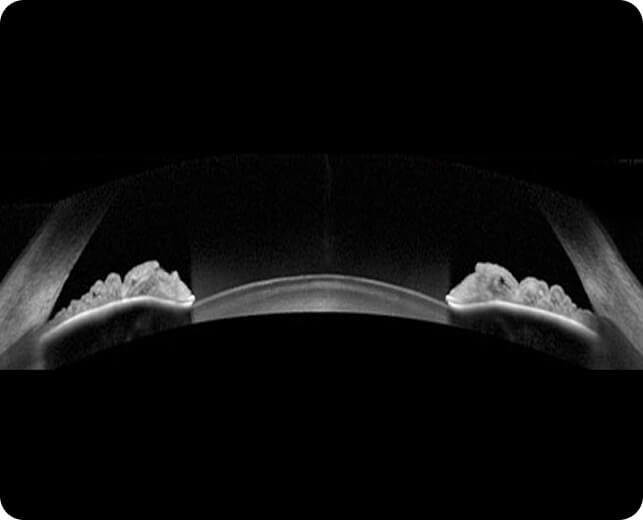

Corneal thickness

• Central Corneal Thickness (CCT) plays a crucial role in determining the accuracy of intraocular pressure (IOP) measurements, which is vital for diagnosing glaucoma

• A thicker cornea can cause artificially high pressure readings, while a thinner cornea may lead to lower pressure readings, potentially masking glaucoma risk

• Measuring the thickness of the cornea is an essential part of any thorough glaucoma investigation, as it provides context for IOP readings and helps determine your true glaucoma risk

• At Edgbaston Eye Clinic, we utilise advanced ophthalmic diagnostic equipment to precisely measure central corneal thickness, ensuring accurate and reliable glaucoma assessments

• CCT measurement is painless and helps create a comprehensive picture of your eye health, allowing for better-tailored glaucoma management and treatment options